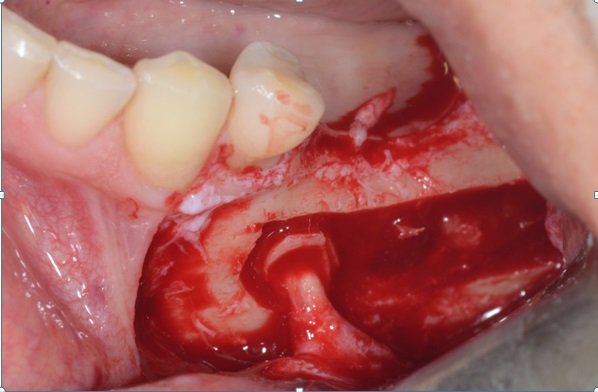

Colocação do guia cirúrgico e marcação do local ideal dos implantes.

Descolamento do nervo alveolar, deixando-o solto dentro do canal. Podemos colocar um túnel check ou fresa deslocando o nervo para o lado em um dos alvéolos artificiais enquanto terminamos a fresagem e colocamos os implantes.

Colocação de PRF (Plasma Rico em Fibrina) sobre o nervo alveolar, desta forma, a sensibilidade do nervo volta com maior rapidez.

Preenchimento da cavidade com HA e PRF.

Sutura feita com vicryl 4-0 e raio-x pós-cirúrgico.